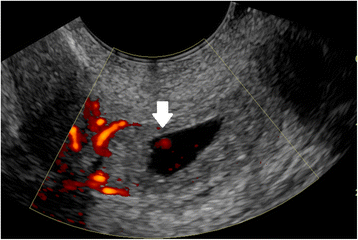

A cervical EP is identified on ultrasound by a distended cervical canal containing a gestational sac with peripheral Doppler flow (Fig. 6), below a closed internal cervical os [102, 103]. The ‘sliding organ’ sign, or movement when pressure is applied with the transvaginal probe, is associated with spontaneous abortions in progress and should be absent in a cervical ectopic pregnancy.

Cervical ectopic pregnancy by transvaginal ultrasound. Doppler shows circumferential flow. The arrow indicates Doppler flow inside the gestational sac, associated with the embryo. Such Doppler flow will not be found in a spontaneous abortion, which may slide down into a similar position at the cervix